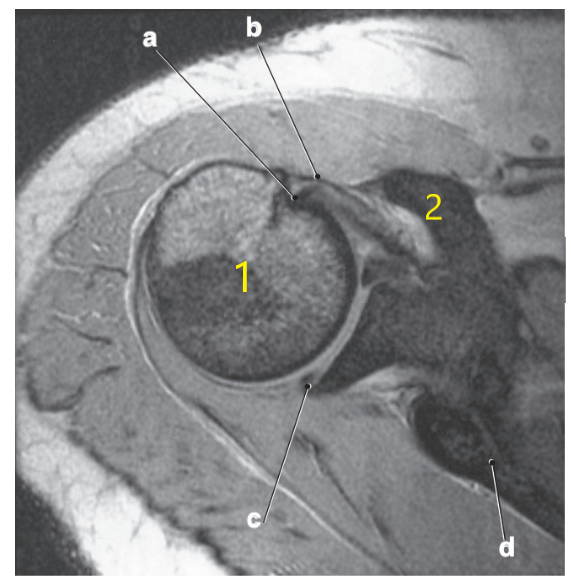

Supraspinatus tendon

Supraspinatus muscle

Superior glenoid labrum

Posterior glenoid labrum